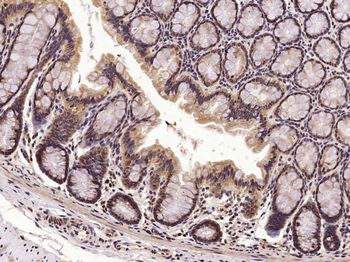

MKP1 Rabbit Polyclonal Antibody

DUSP1

KLH conjugated synthetic peptide derived from human DUSP1 (151-250/367aa)

免疫原:KLH conjugated synthetic peptide derived from human DUSP1 (151-250/367aa)

预测反应性:Bovine, Canine, Equine, Mouse, Rabbit, Rat, Sheep

应用稀释比例:WB=1:500-2000